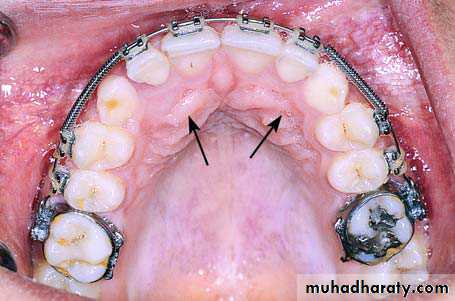

Clinical photograph of the area of impaction